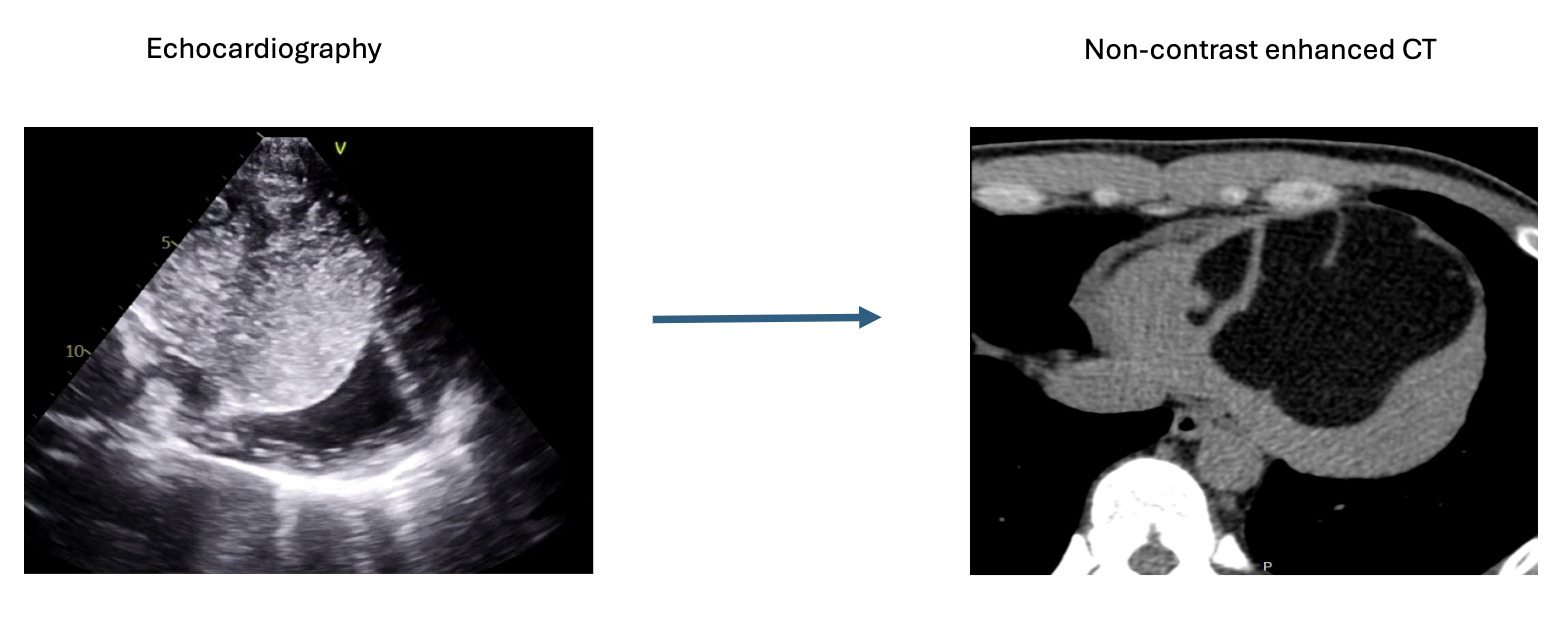

Figure 2. Multimodality CMR and tissue characteristics. (a) Four-chamber and short-axis cine sequences demonstrate a large multilobulated (septated) mass occupying the apical left ventricle and protruding into the right ventricular cavity. (b) Four-chamber STIR imaging shows homogeneous suppressed signal without edema. (c) Axial diffusion-weighted imaging (b = 800) and ADC map confirm absence of diffusion restriction. (d) Four-chamber post-contrast sequence shows no abnormal enhancement. (e) Four-chamber PSIR late gadolinium enhancement sequence confirms absence of contrast uptake, consistent with a benign lesion. (f) Short-axis T1 and T2 mapping demonstrate relaxation times compatible with fat-containing tissue (comparable with subcutaneous fat). Abbreviations: ADC = Apparent Diffusion Coefficient; CMR = Cardiac Magnetic Resonance; DWI = Diffusion-Weighted Imaging; PSIR = Phase-Sensitive Inversion Recovery; SAX = Short Axis; STIR = Short Tau Inversion Recovery..jpg)